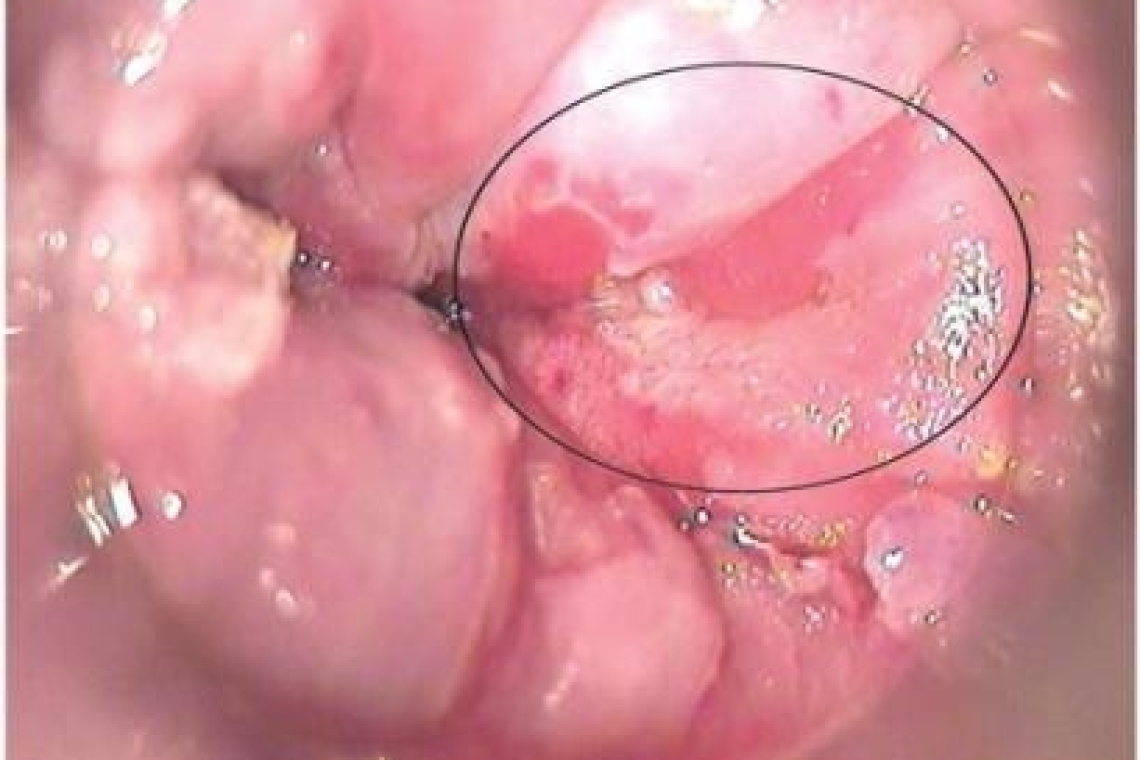

Исследование проводится с целью выявления патологии выходного отдела кишечной трубки, возможное выявление внутреннего геморроя, воспалительных изменений указанной области, дефектов слизистой анального канала- трещины, мацерация, полипы, язвы, свищи.

Самый простой, но не вполне полноценный осмотр анального канала можно выполнить без дополнительных инструментов: пациента просят натужиться как во время акта дефекации, и , руками раздвигаются ягодицы и разводятся стенки анального канала в разных направления. При этом слизистая анального канала выворачивается наружу иногда показывается зубчатая линия и участок прямой кишки с геморроидальными узлами. Так же возможно проведение аноскопии с помощью ректальных зеркал. Инструмент смазывается лубрикантом на всем протяжении вводимых частей, в сложенном состоянии вводится в анальный канал, створки разводятся и осматривается состояние слизистых. В раскрытом состоянии инструмент извлекается,вновь закрывается и вводится с поворотом по окружности на 45-90 градусов. Осматривается другой сектор слизистой. Манипуляции выполняются в 3-4 и более направлениях для полного осмотра всех стенок. Не допустимо поворачивание зеркал при нахождении их в анальном канале. Для исследования требуется дополнительный осветитель.

Существует множество модификаций аноскопов: щелевой Ива, со скошенным вводимым торцом, пластиковые, одноразовые. К подобным инструментам прилагается осветитель встроенный в торцевую часть. Методика аноскопии аналогична осмотру в зеркалах. Вводимая часть смазывается вазелином или другим лубрикантом, аноскоп вместе с обтуратором вводятся в анус, обтуратор извлекается, осматривается сегмент слизистой, инструмент извлекается,вновь вставляется обтуратор, производится поворот и введение в анальный канал для осмотра следующего сегмента, и так по всей окружности.